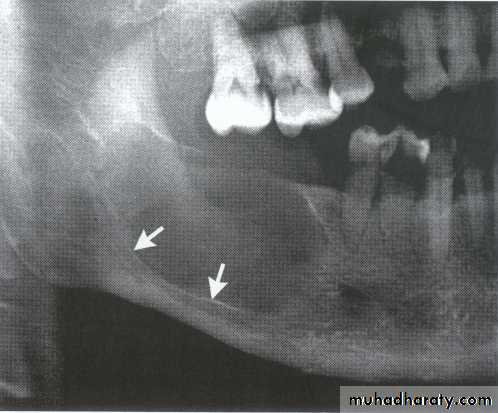

5-year-old boy showing the typical bilateral multilocular lesions of

cherubism affecting the mandible (arrowed).Multiple but separate radiolucent lesions